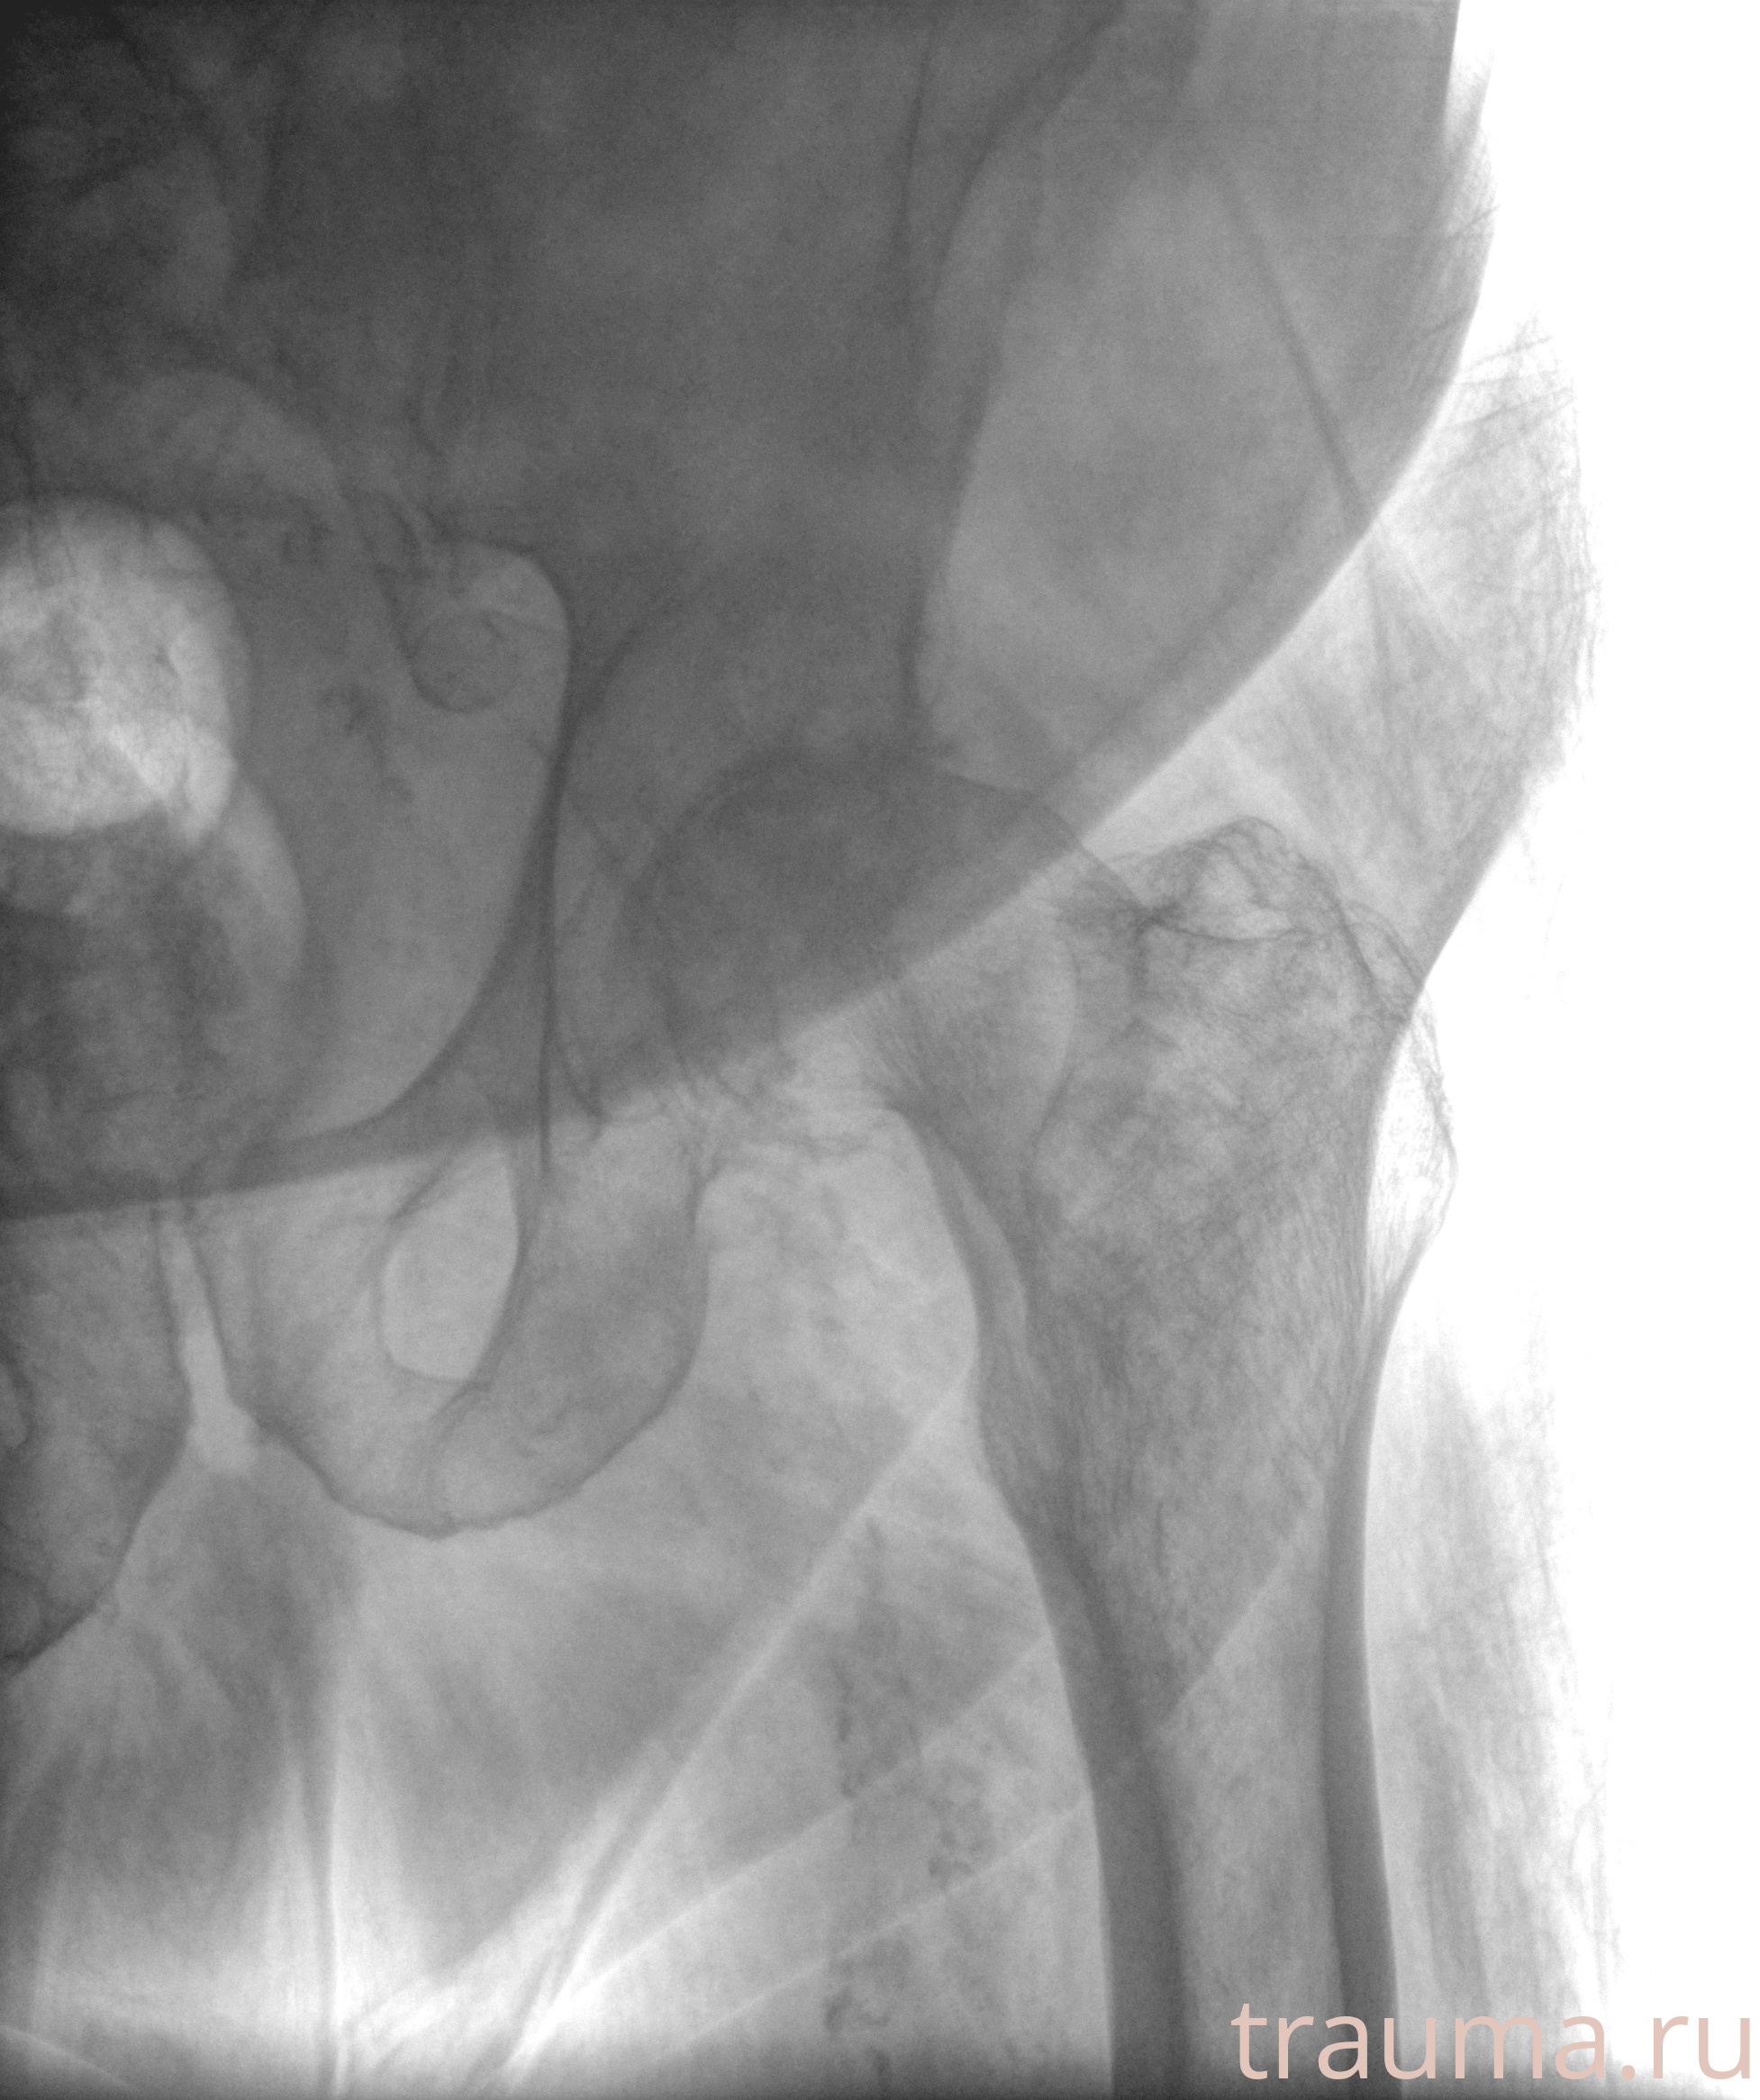

Рентгенограммы

Рентген на дому: по вашему адресу приезжает врач-рентгенолог, травматолог-ортопед с мобильным рентгеновским аппаратом, проводит диагностику травмы или заболевания, делает необходимые рентгенограммы, дает рекомендации по дальнейшему лечению. Получить качественные снимки в домашних условиях возможно благодаря уникальной методике, разработанной МосРентген Центром для института  Склифосовского